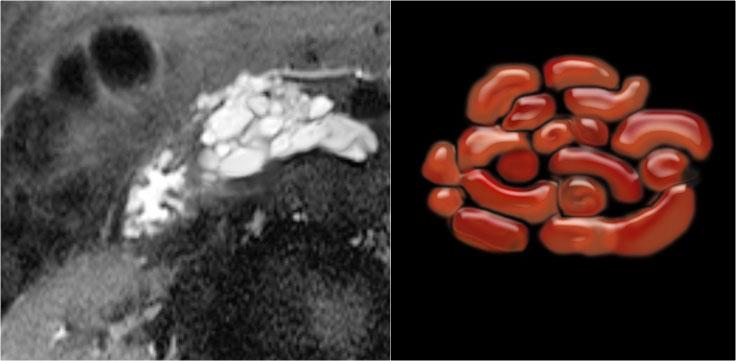

Đặc điểm đặc trưng của u nang tuyến thanh dịch là sẹo trung tâm, đôi khi kèm vôi hóa.

Đôi khi thành phần vi nang của khối u này khó xác định trên CT.

MRI sẽ giúp đánh giá cấu trúc bên trong tốt hơn.

MRI thể hiện rõ hơn các đặc điểm hình thái của tổn thương (hình).

Trên chuỗi xung T2W, tổn thương có dạng đa nang.

Lưu ý vùng giảm tín hiệu trung tâm do sẹo trung tâm kèm vôi hóa.

Mặc dù một số nang có kích thước khá lớn, đây vẫn là hình ảnh đặc trưng của u nang tuyến thanh dịch (dạng đại nang).

Một ví dụ khác về u nang tuyến thanh dịch (Hình).

Hình ảnh sau tiêm thuốc cản quang bên phải cho thấy tổn thương giảm tỷ trọng với vôi hóa trung tâm ở thân tụy và ngấm thuốc nhẹ của các vách ngăn.

Lưu ý rằng trên CT rất khó nhận ra bản chất dạng nang của các tổn thương này và có thể nhầm lẫn với ung thư biểu mô tuyến tụy.

MRI sẽ dễ dàng thể hiện bản chất dạng nang của các tổn thương này (hình).

Chuỗi xung T2W với xóa mỡ (fatsat) thể hiện rõ tổn thương tăng tín hiệu dạng thùy múi với sẹo trung tâm, đây là hình ảnh đặc trưng của SCN.